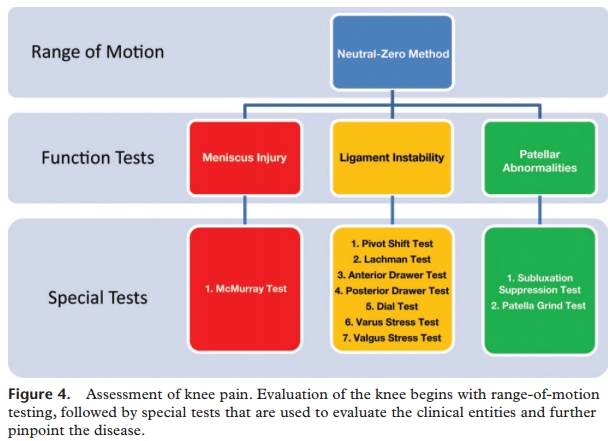

The physician begins by comparing the painful knee with the asymptomatic knee and inspecting the injured knee for erythema, swelling, bruising, and discoloration. The musculature should be symmetric bilaterally.

The knee is then palpated and checked for pain, warmth, and effusion. Point tenderness should be sought, particularly at the patella, tibial tubercle, patellar tendon, quadriceps tendon, anterolateral and anteromedial joint line, medial joint line, and lateral joint line.

The valgus stress test is performed with the patient's leg slightly abducted. The physician places one hand at the lateral aspect of the knee joint and the other hand at the medial aspect of the distal tibia. Next, valgus stress is applied to the knee at both zero degrees (full extension) and 30 degrees of flexion (Figure 4)7. With the knee at zero degrees (i.e., in full extension), the posterior cruciate ligament and the articulation of the femoral condyles with the tibial plateau should stabilize the knee; with the knee at 30 degrees of flexion, application of valgus stress assesses the laxity or integrity of the medial collateral ligament.